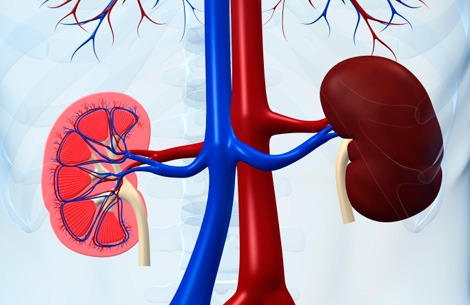

Kidneys are 2 in number, fist-sized and located on either side of the spine below the rib cage. When our bodies digest the protein we eat, the process creates waste products. In the kidneys, millions of tiny blood vessels (capillaries) with even tinier holes in them act as filters. As blood flows through the blood vessels, small molecules such as waste products squeeze through the holes. These waste products become part of the urine. Useful substances, such as protein and red blood cells, are too big to pass through the holes in the filter and stay in the blood.

Each kidney has large number (approximately one million) nephrons- each containing individualized filtering system called glomerulus. The glomerulus has multiple blood vessels and is attached to a tubule. The blood containing impurities from the body, reaches the blood vessels in the glomerulus. In these vessels the filtration process takes place and the remaining fluid passes along the tubule. In the tubule the chemicals and water are either added or extracted according to the body’s needs. The final product of this process is the urine we eliminate. Each glomerulus functions individually and the total waste is collected and sent to the urinary bladder.

The kidneys filter and return to the bloodstream more than 200 liters of fluid every 24 hours. Approximately two liters are eliminated as urine, which flows from the kidneys through the urethra to the bladder, where it is stored for up to eight hours. The urine carries with it the waste filtered by the kidneys.